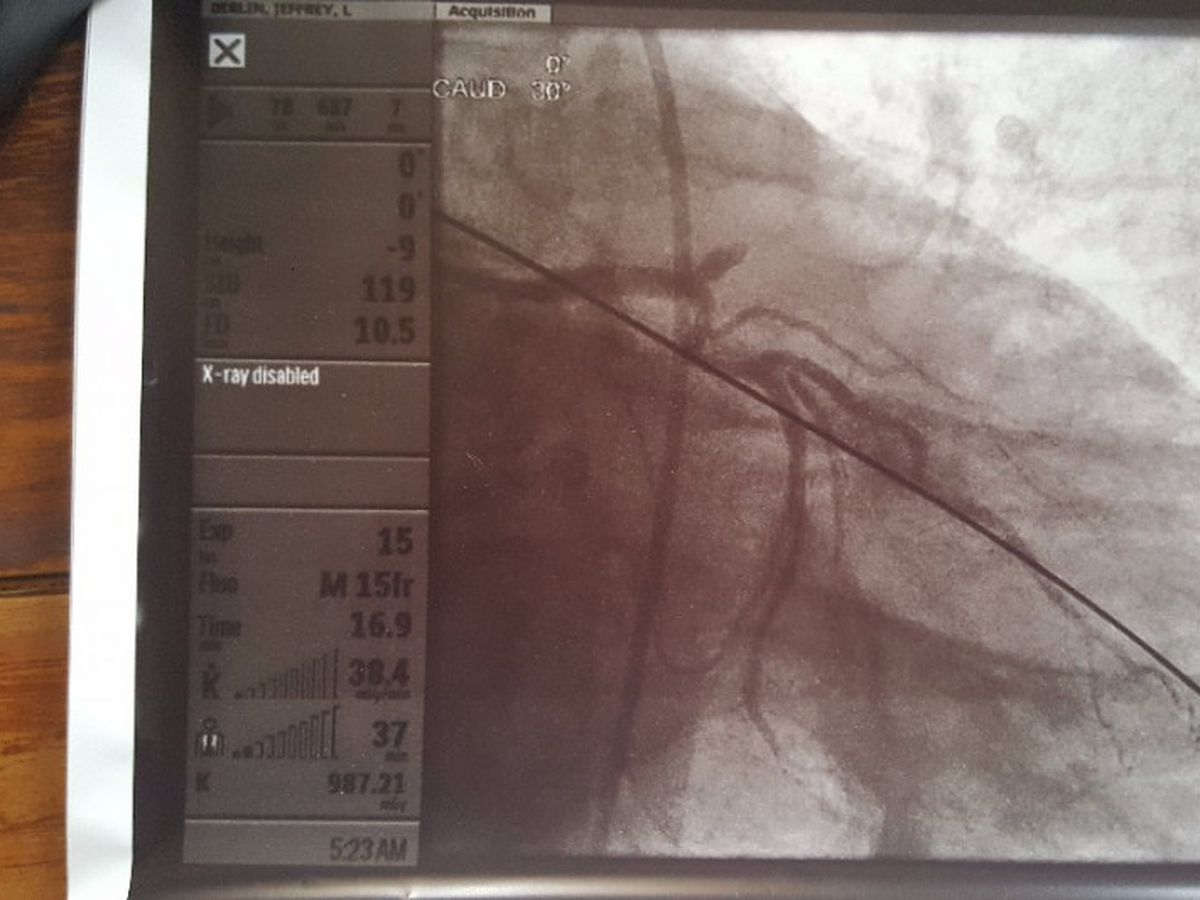

My wife and I were cycling on a flat trail on Sunday, August 13th, and I was having a bit of chest pain all during the ride. I blew it off as indigestion since I just passed a stress test last month. Late Monday evening, the pain got so bad I broke down and let my wife take me to the ER. I was having a heart attack. Turns out it was the "Widowmaker" artery that was 100% blocked.

After 2 stents and 48 hr with an aortic balloon, I'm stabilized. The hopsital experience is the least of my worries. The medication that I will have to be on for the rest of my life is going to be the problem. It is expensive and most of the cost is not covered under our insurance.